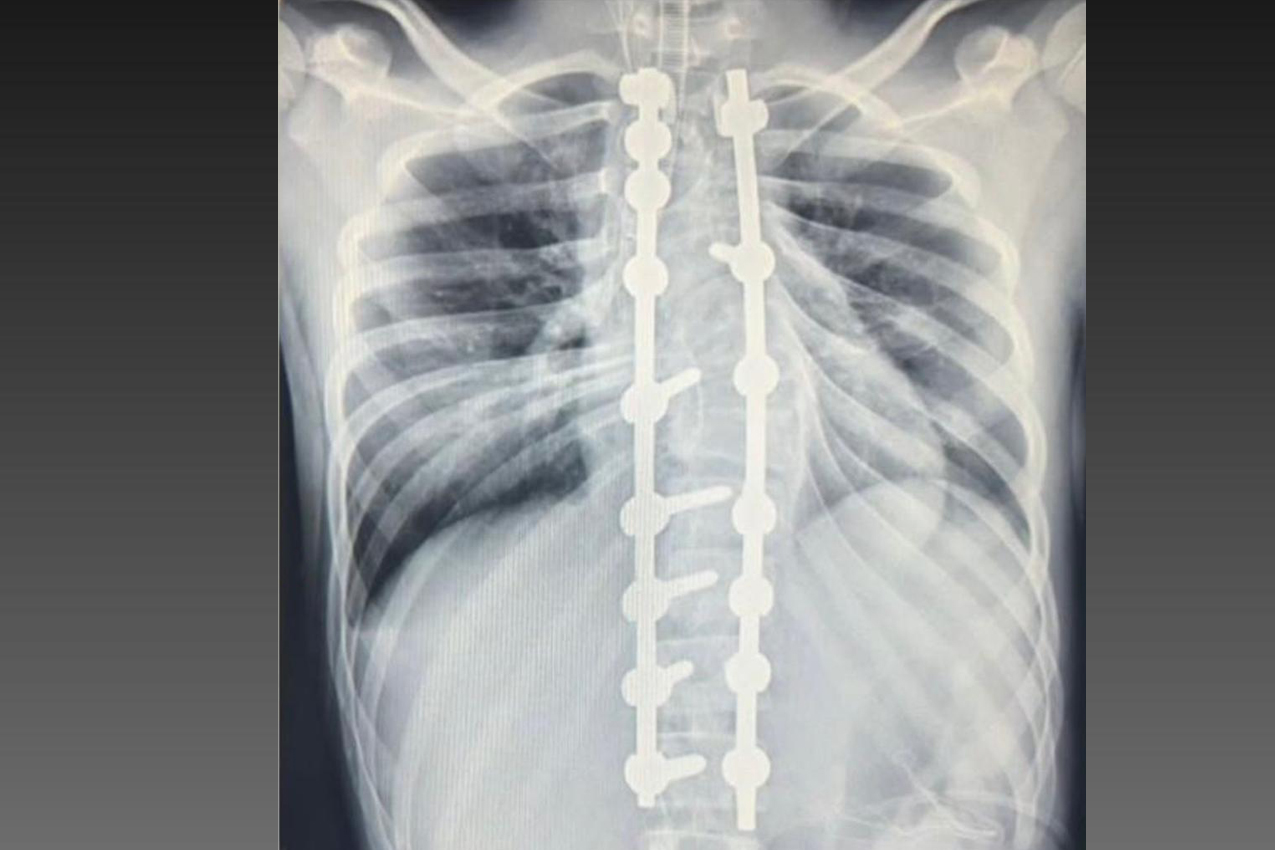

Laura era portadora de escoliose e, em agosto de 2025, realizou a cirurgia de correção da coluna, o que lhe permitirá ter uma vida normal de agora em diante. Moradora de Bom Sucesso do Sul, região Oeste do Paraná, é acostumada a andar a cavalo, mas com o problema na coluna a prática estava longe de ser prazerosa.

De abril de 2023 até dezembro de 2025, foram realizadas 209 cirurgias no Departamento de Deformidades Pediátricas da Coluna Vertebral do CHT, que envolve o próprio Hospital do Trabalhador, o Ambulatório Médico de Especialidades (AME) e o Hospital de Reabilitação.

“O projeto iniciado em 2023 aqui no CHT já atendeu um grande número de pacientes. Hoje, são poucos os locais de referência para atendimento desses pacientes e temos toda essa estrutura aqui no Paraná. Foram mais de 200 casos operados e centenas de pacientes tratados. Tratamento que vai desde os conservadores, como exercício e fisioterapia, até o uso de coletes gessados e de polipropileno e casos cirúrgicos”.

A cirurgia ocorreu no dia 28 de julho e uma segunda etapa em quatro de agosto. Desde então, Joyce viu a sua vida mudar. “Nasci com a escoliose e tinha muita dificuldade e limitações para caminhar e perda de movimento. Havia dias em que eu não levantava da cama. Quando saia de casa recebia olhares de julgamento das pessoas, que era o que mais me incomodava. Depois da cirurgia, posso dizer que eu tenho uma nova vida. Eu venci a batalha”, relatou.